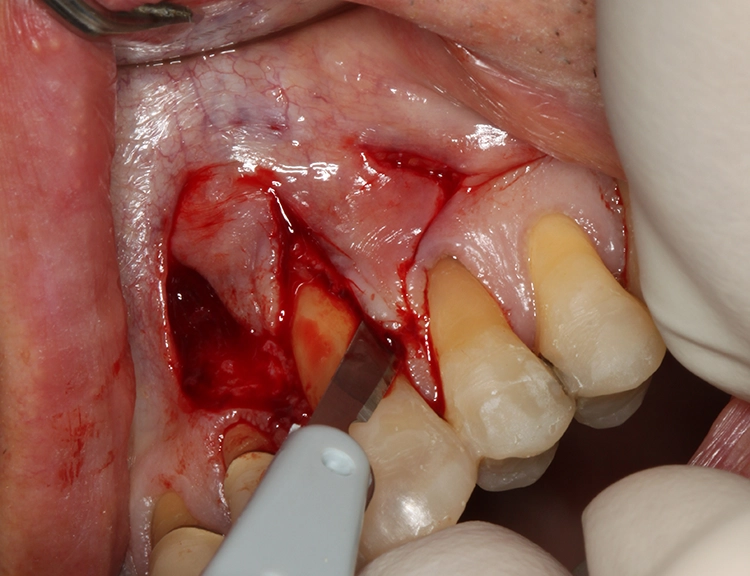

Für die plastische Rezessionsdeckung an den Zähnen 13 und 23 mithilfe von doppelten Papillalappen nach Cohnen und Ross [2], Bindegewebetransplantaten und Schmelz-Matrix-Proteinderivat wurde die Schnittführung mit Split-Flap-Bildung so gewählt, dass möglichst viel keratinisierte Gingiva generiert werden konnte und der Mindestabstand zu den Nachbarparodontien von 1 mm eingehalten wurde (Abb. 13). Ein Gewebekeil wurde apikal der Rezession entfernt und vorerst nur ein Läppchen gesplittet (Abb. 14). Die beiden gesplitteten Läppchen wurden vernäht, wobei ein Mukosaläppchen noch unmobilisiert blieb, um das Aneinandernähen zu erleichtern. Das Vernähen erfolgte von koronal nach apikal, danach wurde das zweite Läppchen vollständig mobilisiert (Abb. 15).

Es erfolgte eine plastische Rezessionsdeckung an den Zähnen 13 und 23 mit doppelten Papillenlappen nach Cohen et al. [2] unter Einsatz von Bindegewebetransplantaten und Schmelz-Matrix-Proteinderivat.